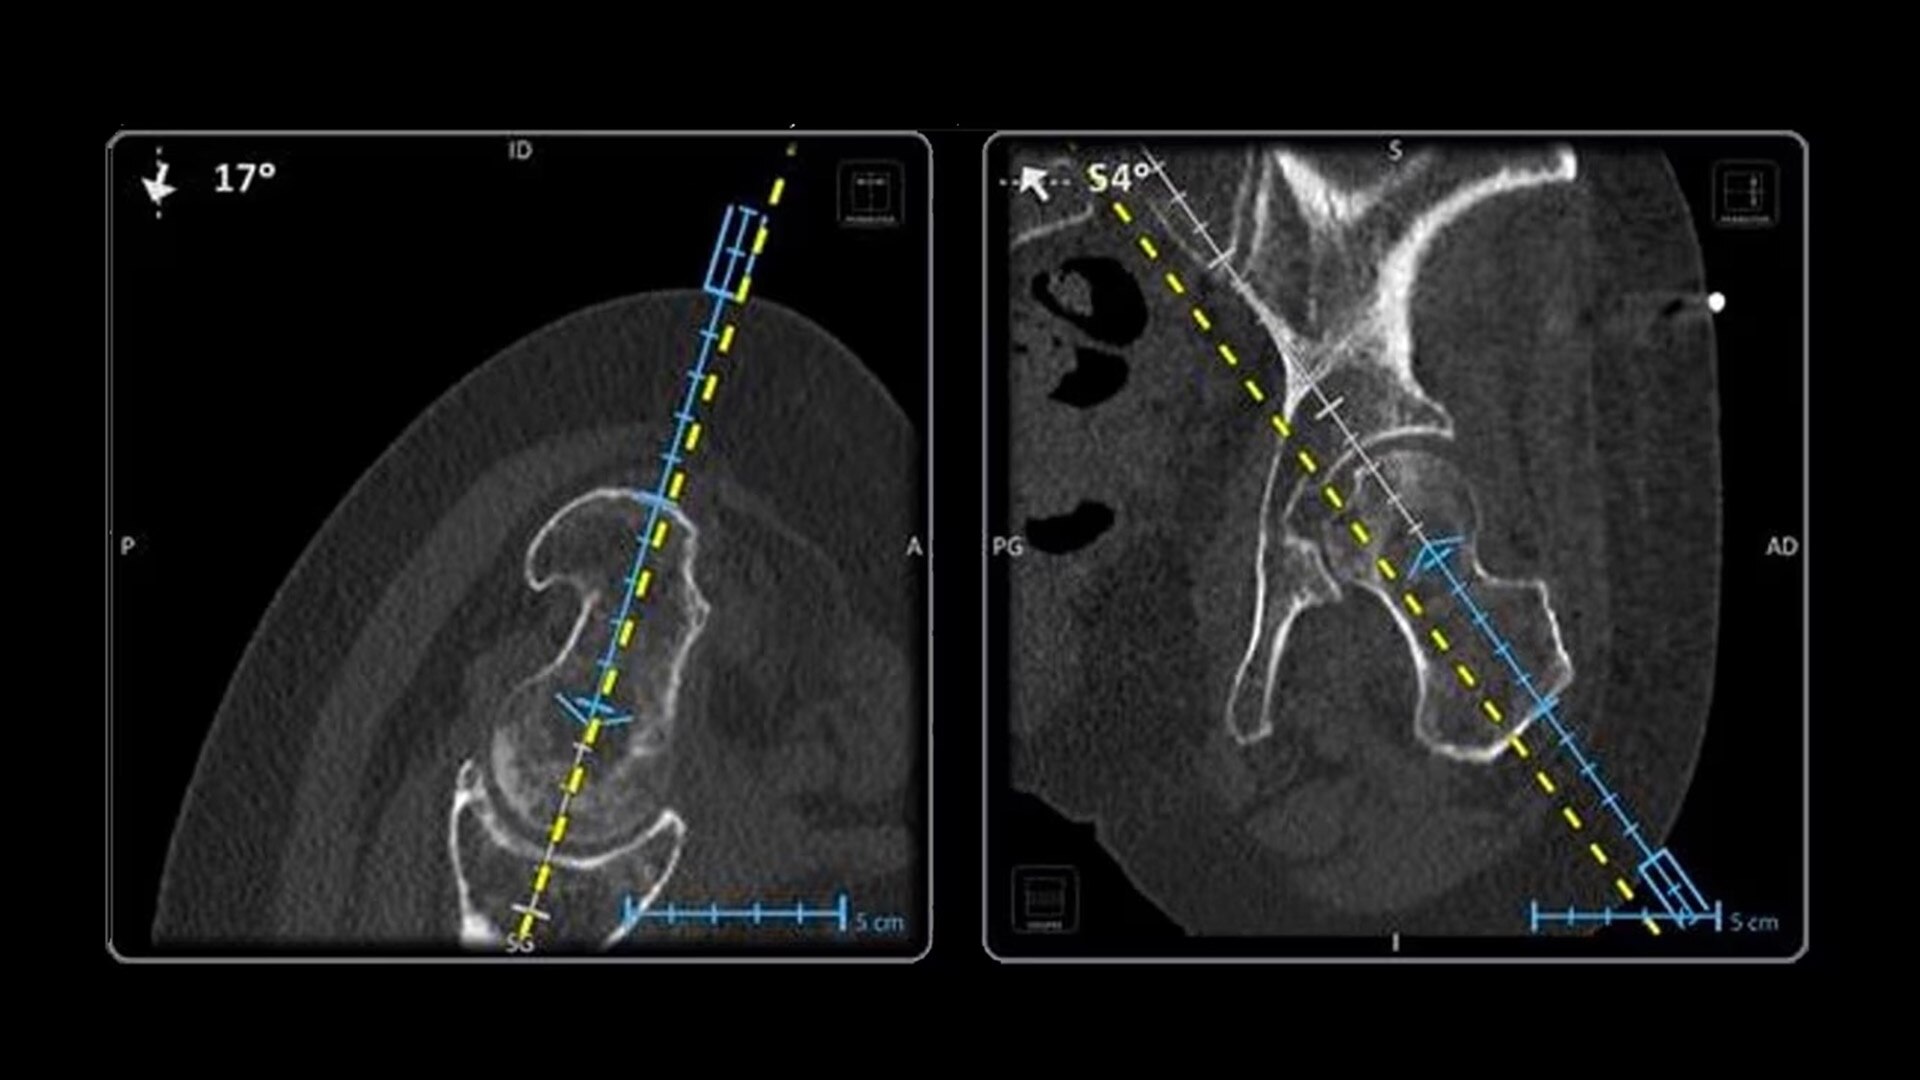

In interventional radiology, the success of the percutaneous procedure depends on correct needle positioning. The Imactis system helps the radiologist place one or more needles with great accuracy, in less time and with fewer control scans.

The CT navigation solution optimizes the efficiency and potentially helps to improve clinical outcomes of biopsies, thermoablations, drainages, infiltrations, electroporations and osteosynthesis.

With real-time image reconstruction, live interactive navigation and no limit in angulation, the optimal clinical choices are clear.

Live 3D needle tracking, precise reproduction of your planned trajectory and continuous needle depth measurement help ensure optimal needle placement.